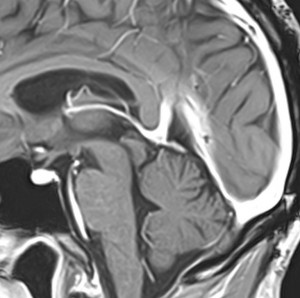

上矢状洞髄膜腫 superior sagittal sinus meningioma

また別な例です。1986年13歳の時に2度の開頭手術を受けましたが,全摘出できずにそのまま経過観察されました。

左の画像は1997年の術前のものです。これを2回に分けて全摘出しました。上矢状洞はやはり冠状縫合のあたりから静脈洞交会まで摘出しました。その下の大脳鎌も全て摘出したので,直静脈洞の上壁を開けることになり,直静脈洞からの激しい出血があり縫合して直静脈洞形成をするのが大変でした。手術後16年が経過しますが再発していませんし,社会人として普通に暮らせています。

この例が教えてくれることは,上矢状静脈洞は全長にわたり切除してしまっても,神経脱落症状を出さないで普通に生きて行かれるということです。